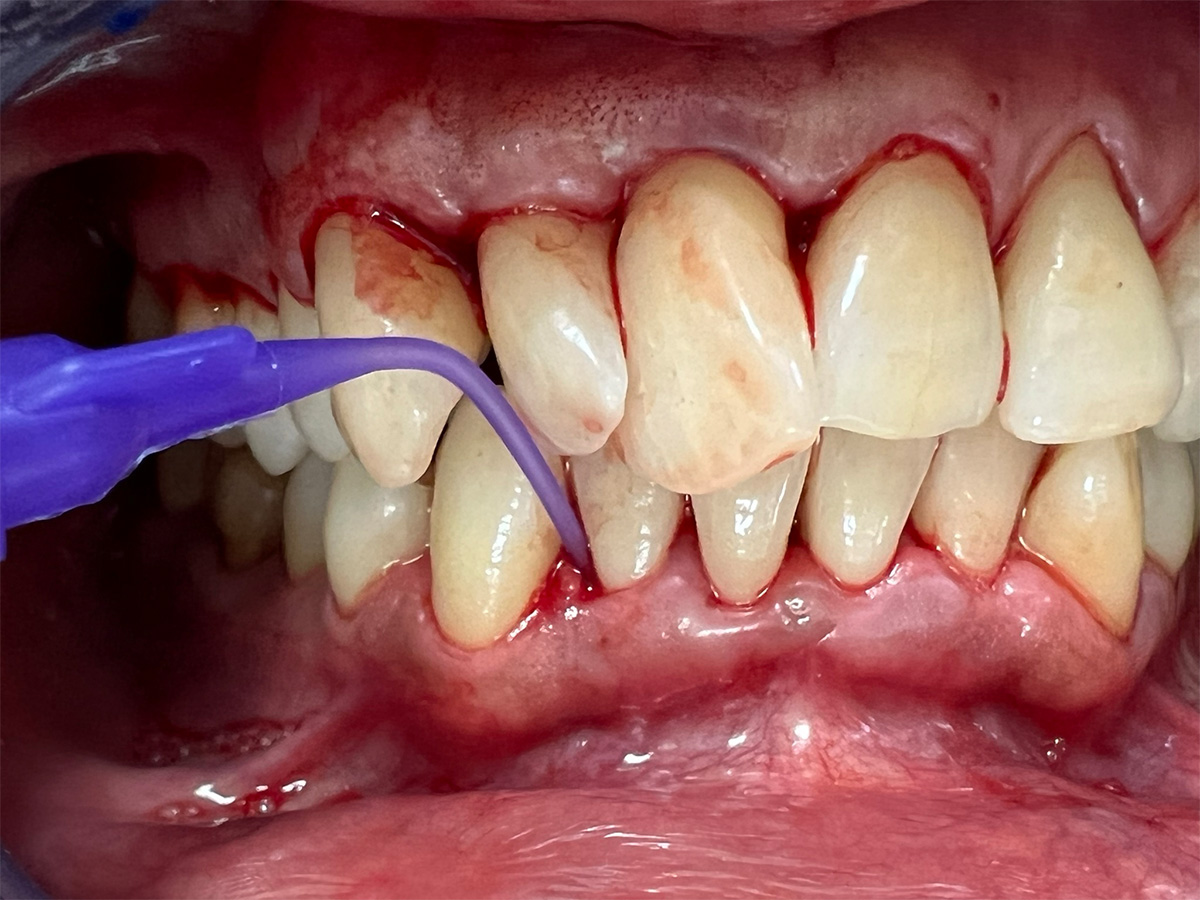

In diesem Workshop erhalten Sie umfassendes Wissen für die Behandlung von Parodontitis-Patientenen. Zunächst führt Sie Yvonne Gebhardt durch moderne subgingivale Behandlungskonzepte – das Herzstück der PA-Therapie. Anschließend erklärt Ihnen Sonja Steinert die faszinierenden Zusammenhänge des Knochenstoffwechsels: Wie Entzündungen den Knochenabbau fördern und wie Sie mit gezielter Therapie und Vitamin D gegensteuern können.

• Subgingivales Behandlungskonzept

• Anwendung von Pulverstrahl-/Ultraschallgeräten